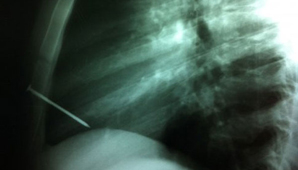

Precisó que el clavo, de ocho centímetros de largo, había atravesado el esternón y el ventrículo derecho del corazón, y quedó alojado en la cavidad cardíaca.